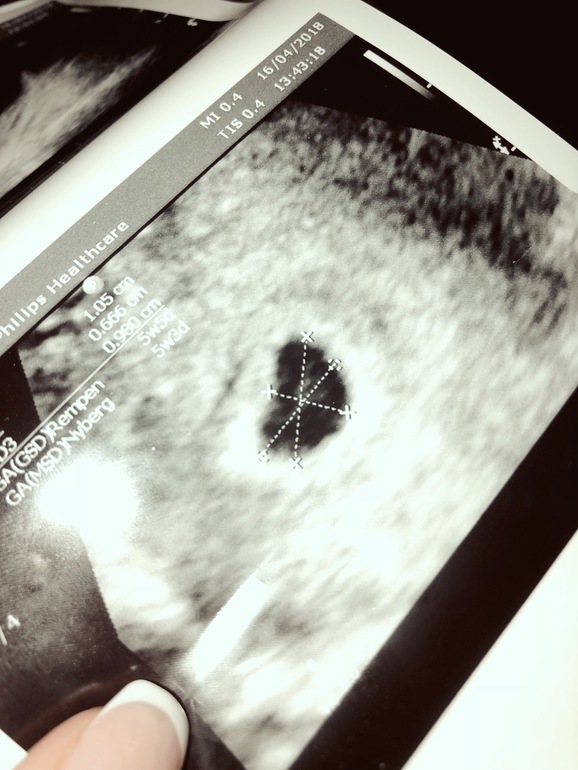

УЗИ, КТГ, доплерДевочки , знатоки , скажите когда у вас появился эмбрион ? И это нормально что 2 дня отставания ? По мес 5+5, по УЗИ 5+3. Эмбриона не видно (( размера пя единого нет , только такие - 1.05х0.66х0.98. И скажите , на фотке там в пя это жм ? И что это за ниточка тянется? Заранее спасибо за ответ )))